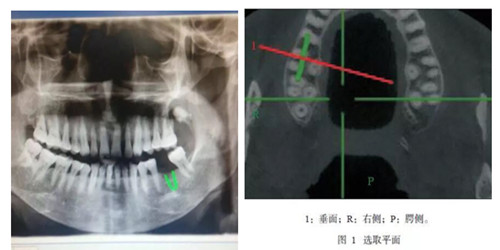

CBCT是一种锥形束投照计算机重组断层影像设备,可用于种植、颌面外科、正畸、牙体牙髓病、牙周病等方面的检查。通过口腔CT的立体影像可以全面了解颌骨形态、牙齿周围的解剖结构,牙根的位置与形态、下颌神经管的走向和范围、上颌窦底的位置及上牙牙根与上颌窦的关系、下牙牙根与下颌神经管的位置关系等肉眼不可见的组织结构。

CBCT具有特点:图像分辨清晰、重建速度快速、重建时间低于15S,成像范围合理、伪影校正技术独特,避免重叠等,操作简单便捷,一次扫描即可获得全口腔双牙列三维立体影像 等一系列特点。与传统CT相比CBCT的辐射量更低、牙齿与颌骨成像更加清晰。我院CBCT附送患者一张影像刻录光盘,观看胶片不需要观片灯,直接在医生电脑上即可动态观看图像;消除患者等待烦恼。